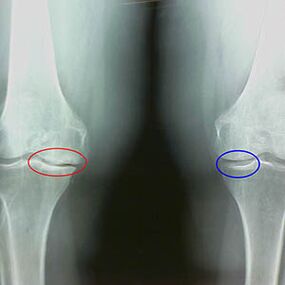

Określenie stopnia artrozy występuje przez x -rayujawniając udział w patologicznym procesie struktur kostnych. Ich zmiana wskazuje, że system mięśni jest nierównowagi od 5-10 lat. Z reguły ludzie Przez kilka lat doświadczają bólu.

Na pierwszym stadium artrozy, który jest wykrywany przez przypadek, następuje niewielki wzrost ostrogi kości. Wzrost pojawia się w miejscach o największej niestabilności stawu. Zazwyczaj pacjenci rzadko doświadczają bólu lub dyskomfortu podczas ruchu.

Drugi etap artrozy jest uważany za łatwy. Radiograf ujawnia znaczne ostrogi kości, ale nie wpływa to chrząstka. Ilość płynu maziowego jest zmniejszona, ale objawy bólu pojawiają się po długim chodzeniu i bieganiu, sztywności stawu i bólu podczas zginania i pozycji na kolanach.

Wczesne cechy X -Brak drugiego etapu artryozy kolanowej:

- spiczaste krawędzie guzków interpisji piszczelowej, gdzie przymocowane jest więzadło krzyżowe;

- Zwężenie stawu po stronie środkowej;

- Spiczaste krawędzie kłykcji kości po stronie przyśrodkowych, rzadziej w bocznej - w zależności od rozwoju deformacji stawów Valgusa lub zmiennego.

Dla drugiego etapu w Larsen Zwężenie wspólnej luki o ponad 50% jest charakterystyczne, ale można to sprawdzić tylko w dynamice lub porównaniu z różnym połączeniem.

Radiograf pokazuje obecność osteofitów, zmianę przestrzeni między kościami kości udowej i piszczelowej, co wskazuje na utratę chrząstki w kolanie. Czasami X -Ray stawów kolanowych wykazuje znaczące oznaki zużycia chrząstki, ale pacjenci nie doświadczają znaczącego bólu.Przeciwnie, artroza pierwszego etapu może zakłócić funkcję kolana, ponieważ przyczyną bólu są mięśnie hipotoniczne.